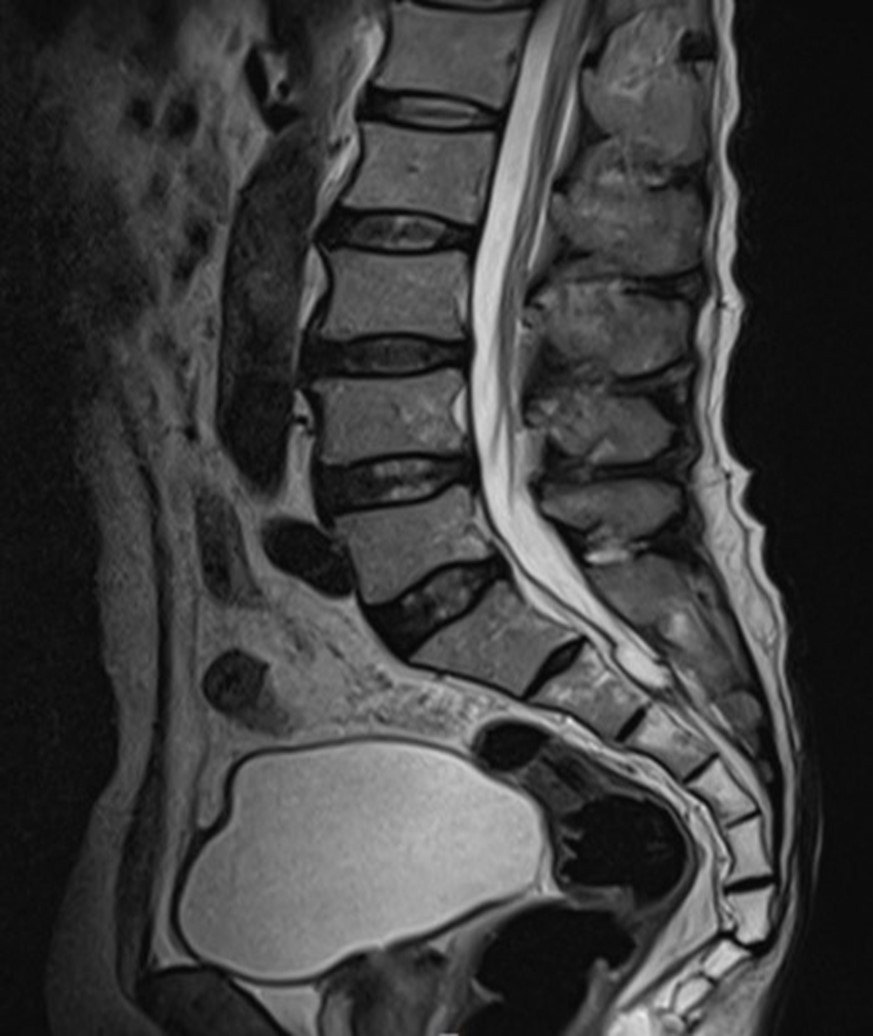

그림2.jpg 촬영 일시: 2025.01.04

<Fig 1. 허리 MRI>

MRI와 근전도검사를 통해 확인된 결과는

'다발성 말초신경병증'이었습니다.

쉽게 말해서, 항암제가 암세포를 공격하는 과정에서

손발 끝까지 이어지는 가느다란 신경들도

함께 손상을 받게 된 상황이었던 거죠.